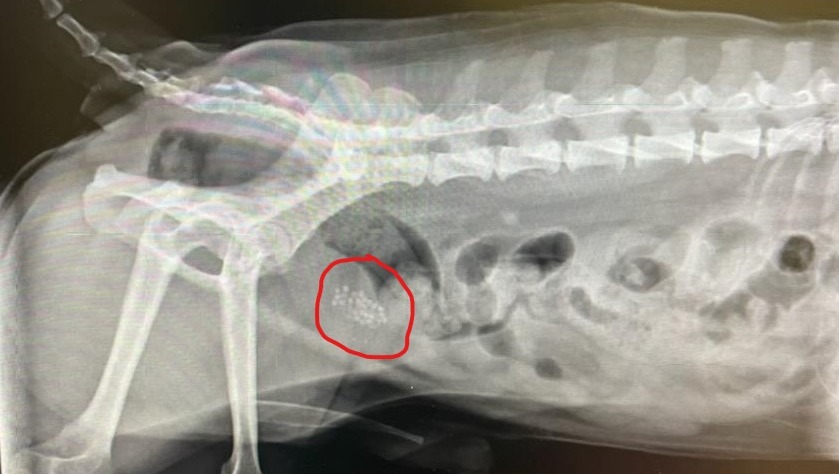

His most recent comprehensive exam showed he currently has over 30 stones in his bladder (see attached photos). At this point, due to his previous four surgeries, our only option for him is to have a Scrotal Urethrostomy surgery. This surgery aims to widen the urethral opening to allow the passage of stones. The goal of this surgery is to get him relief from undergoing continuous surgeries and give him a chance at a healthy and happy life. Unfortunately, his surgery will cost $6000 as his insurance does not cover it.